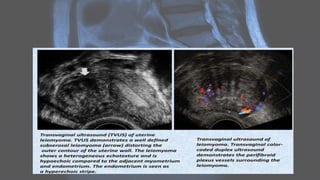

Uterine leiomyomas • Uterineleiomyomas, also known as uterine fibroids, are benign tumors of myometrial origin and are the most common solid benign uterine neoplasms. They are a common incidental finding on imaging and rarely cause diagnostic dilemma. Plain radiograph • Popcorn calcification within the pelvis may suggest the diagnosis.

Ultrasound • Ultrasound isused to diagnose the presence and monitor the growth of fibroids: • uncomplicated leiomyomas are usually hypoechoic, but can be isoechoic, or even hyperechoic compared to normal myometrium • calcification is seen as echogenic foci with shadowing • cystic areas of necrosis or degeneration may be seen • Venetian blind artifact may be seen but edge shadowing +/- dense posterior shadowing from calcification is also typically seen 17

CT • fibroids areusually seen as soft tissue density lesions and may exhibit coarse peripheral or central calcification • they may distort the usually smooth uterine contour • enhancement pattern is variable